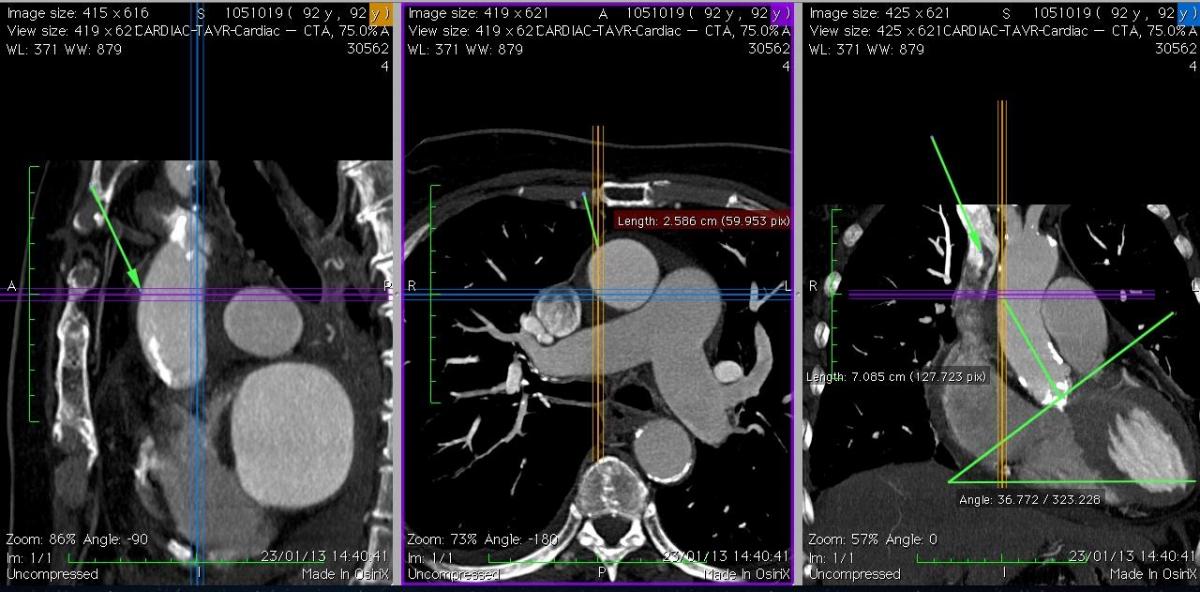

Fig. 5A: Case 1. The coronal view (right picture) shows a “vertical” aorta, and the ideal coaxial direction of the delivery system, with a suitable puncture site at 7 cm. The axial view (middle) shows that the ascending aorta is central (behind the sternum) and free of calcification at the level of the projected puncture site.